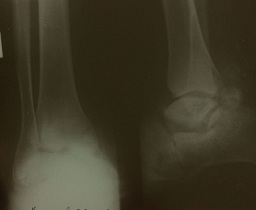

2. рис.1 б | |

| Тема | ||

| Тип | author.submit.suppFile.figureResearchMaterials | |

Посмотреть

(8KB)